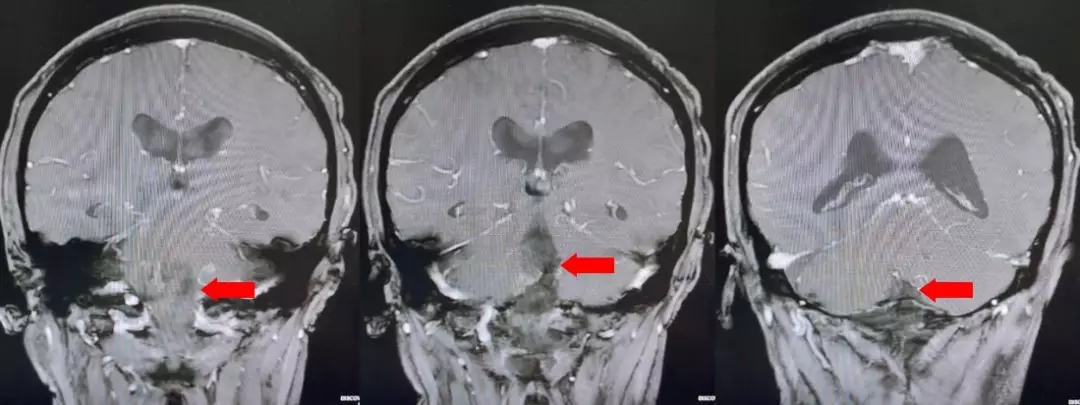

颅脑核磁T1W1成像

颅脑核磁增强扫描

颅脑核磁平扫加增强扫描:

第四脑室内见一巨大形态不规则的异常信号影,肿瘤信号不均匀,T1W1呈略低信号影,T2W1呈稍高及高信号影,增强扫描可见肿瘤不均匀明显强化。肿瘤充满整个四脑室,大小约44*37*55mm,上方接近四脑室顶部,下方至颈2脊髓平面上方,已经部分侵袭桥脑、延髓,局部边界不清,无明显间隙,脑干局部明显受压变形。肿瘤上方脑室系统扩张,出现梗阻性脑积水征象。

影像诊断:1.第四脑室内占位性病变,室管膜瘤可能性大;2.梗阻性脑积水。